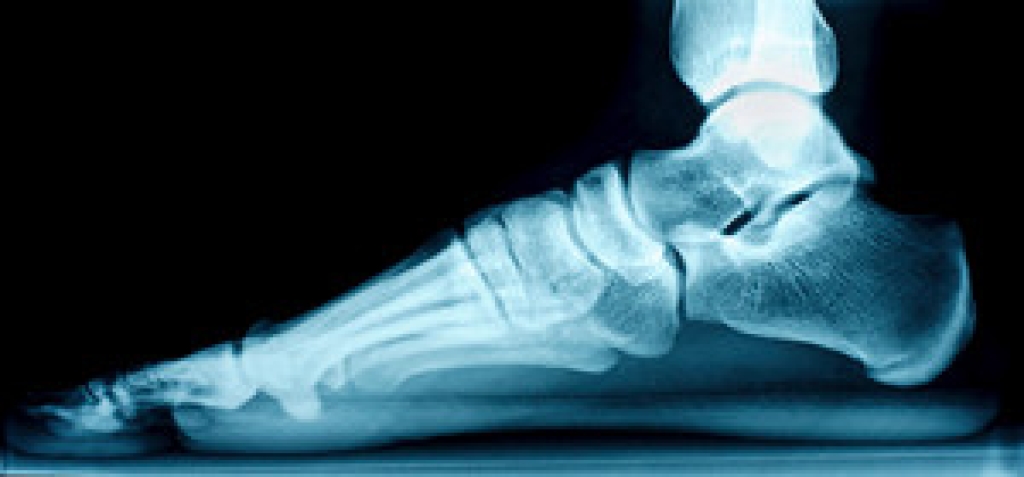

Achilles tendon injuries are diagnosed by a thorough physical evaluation, which can include an MRI. Treatment involves rest, physical therapy, and in some cases, surgery. However, various preventative measures can be taken to avoid these injuries, such as: